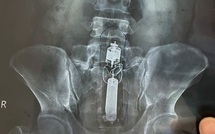

Nam bệnh nhân nhập viện cấp cứu vì kẹt đồ chơi tình dục trong trực tràng

TTO - Bệnh viện Quân y 175 TP.HCM cho biết vừa nội soi lấy dị vật là đồ chơi tình dục cho một bệnh nhân nam do trong quá trình sử dụng đã để 'đồ chơi' trôi xuống trực tràng.